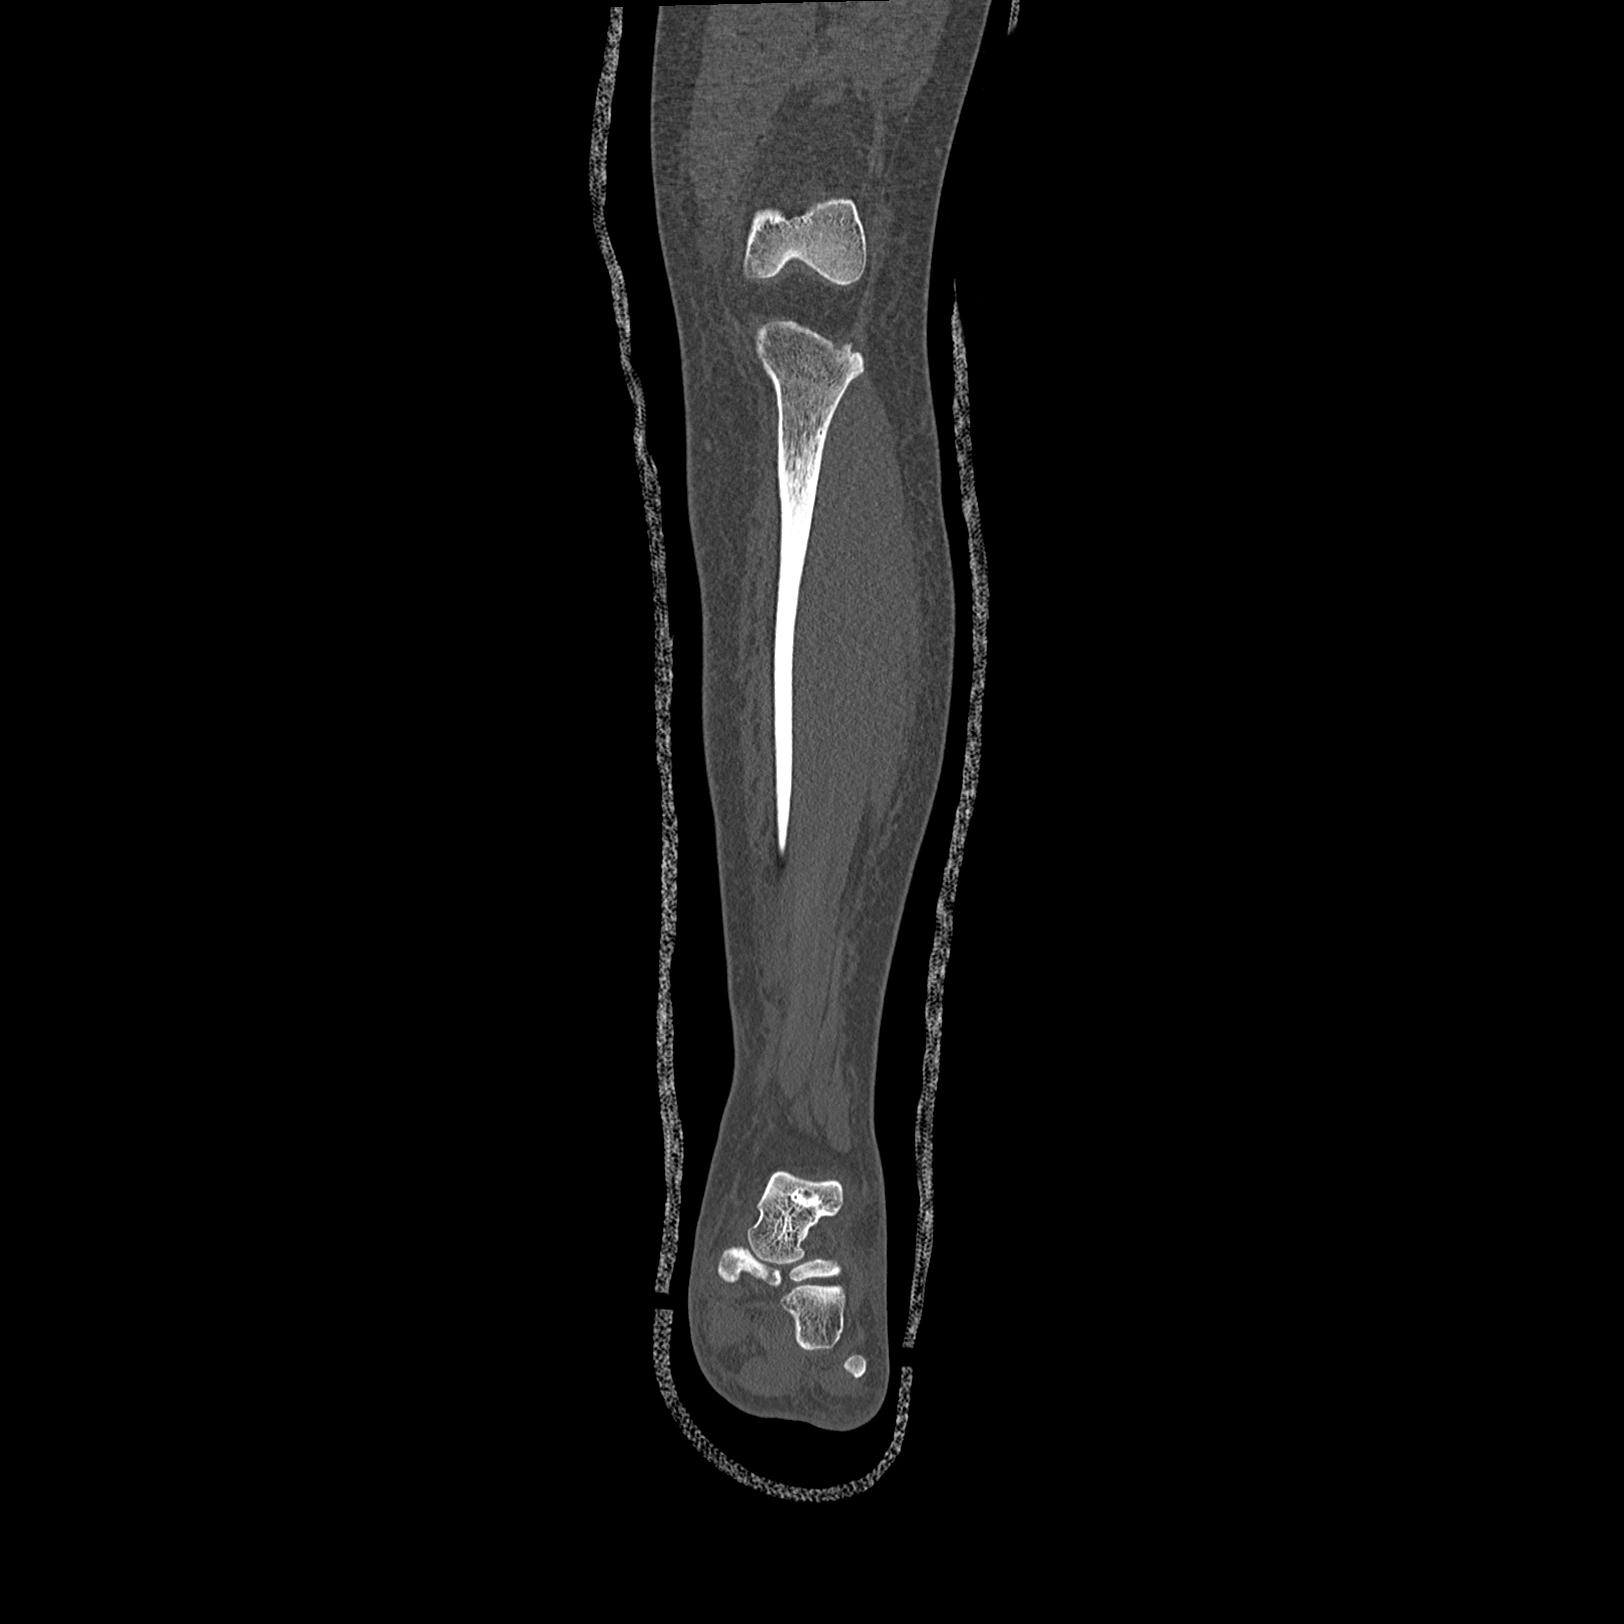

102803 1/12(キウスなし) 1/27 左下腿 4R 30歳女性 左脛骨軸内釘